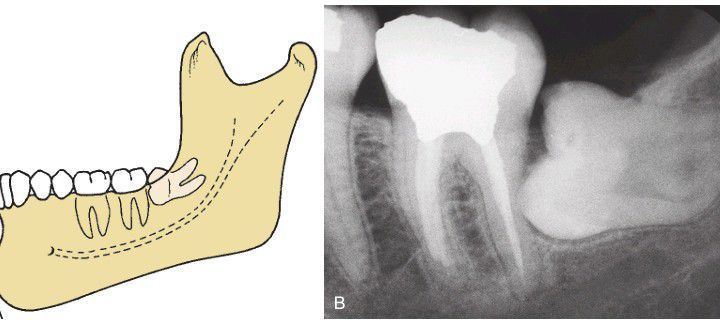

A) Horizontal impaction—an uncommon and more difficult to remove impaction than a mesioangular impaction. (B) The occlusal surface of the horizontal impacted third molar is usually immediately adjacent to the root of the second molar, which often produces early severe periodontal disease.